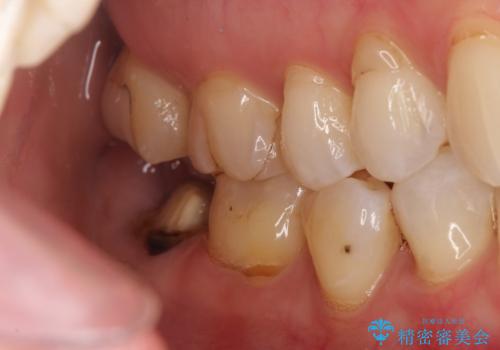

- 他院で治療した被せ物が取れたを主訴に来院された患者様です。被せものが外れた隣の歯もプラスチックの詰め物の劣化や歯に亀裂があったためオールセラミッククランで治療を行いました。

昔詰めたプラスチックの詰め物の範囲が大きいのと破折のリスクや強度の担保のためインレーではなくクラウンで治療を行いました。